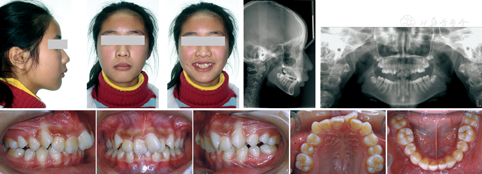

患者,女,13岁,主诉:牙齿不整齐,龅牙。患者全身健康状况良好,无既往患病史。

正面观:面部左右不对称,右侧稍丰满,上下唇自然闭合。侧面观:面型稍凸,下颌后缩,平均生长型,露龈微笑。恒牙列,17、27未萌,32、42先天缺失。前牙覆

Ⅲ度。磨牙关系中性。上牙列拥挤度7 mm,下牙列散隙2 mm。上颌中线左偏3 mm,下颌中线无异常(图1)。牙龈无明显肿胀,口腔卫生一般。双侧颞下颌关节无弹响,无明显压痛。

像及X线片

像及X线片头颅侧位片示该患者骨性Ⅱ类,下颌后缩,均角。上前牙舌侧倾斜,下前牙较直立。曲面断层片示全口牙牙根及牙槽骨无明显吸收。见图1。